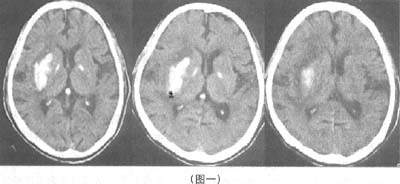

如图一就是一个出血灶。出血灶在CT里表现是高密度的。什么叫高密度,就是CT里白的地方。越亮越白的就说密度越高,越黑越模糊的就说密度越低。如图就是高密度影,有脑内高密度灶。如果有黑糊糊的,比周围都要黑得多的,就是典型的缺血梗塞灶。